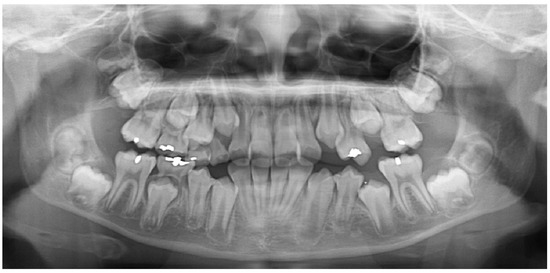

3.3. Working Example